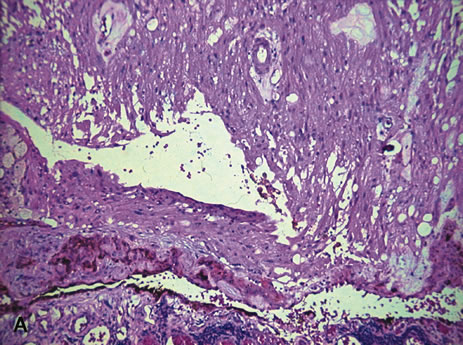

In 1931, Callender classified uveal melanomas based on cytologic features.166 He described six groups, four of which were based on cytology and two on other histologic features. The groups based on cytology were tumors composed of (1) spindle-A cells, (2) spindle-B cells (Fig. 26), (3) epithelioid cells (Fig. 27), (4) a mixture of epithelioid and spindle cells (Fig. 28). The fifth group consisted of tumors with a fascicular pattern, and the the sixth group was composed of tumors that could not be classified in the other groups because of extensive necrosis (Fig. 29). Spindle cells are described as fusiform and arranged in tightly cohesive bundles. The plasma membranes of the cells are indistinct and have a syncytial appearance. Spindle-A cells have a slender nucleus with fine chromatin and a longitudinal fold in the nuclear envelope that gives the appearance of a line. Spindle-B cells have a slightly plumper nucleus, coarser chromatin, and a more prominent and eosinophillic nucleolus. Epithelioid cells are larger and more pleomorphic. They have an abundant glassy cytoplasm, a polyhedral shape, and a distinct cell border and are less cohesive. Epothelioid cells tend to have a larger and rounder nucleus than the other types, with a more angular nuclear envelope and irregular indentations. The chromatin is coarse and marginated, and large eosinophillic nucleoli are present.

Fig. 26. Choroidal melanoma. Note spindle-B melanoma cells with nucleoli. (Hemotoxylin-eosin ×160.)

Fig. 27. Choroidal melanoma. The epithelioid melanoma cells show large nuclei and prominent nucleoli. (Hemotoxylin-eosin ×160.)

Fig. 28. Choroidal melanoma. The tumor shows a mixture of spindle cells and epithelioid cells. Both spindle A and spindle B cells are present. (Hemotoxylin-eosin ×160.)

Fig. 29. Choroidal melanoma. Necrotic tumor cells are mixed with melanophages. (Hemotoxylin-eosin ×200.)